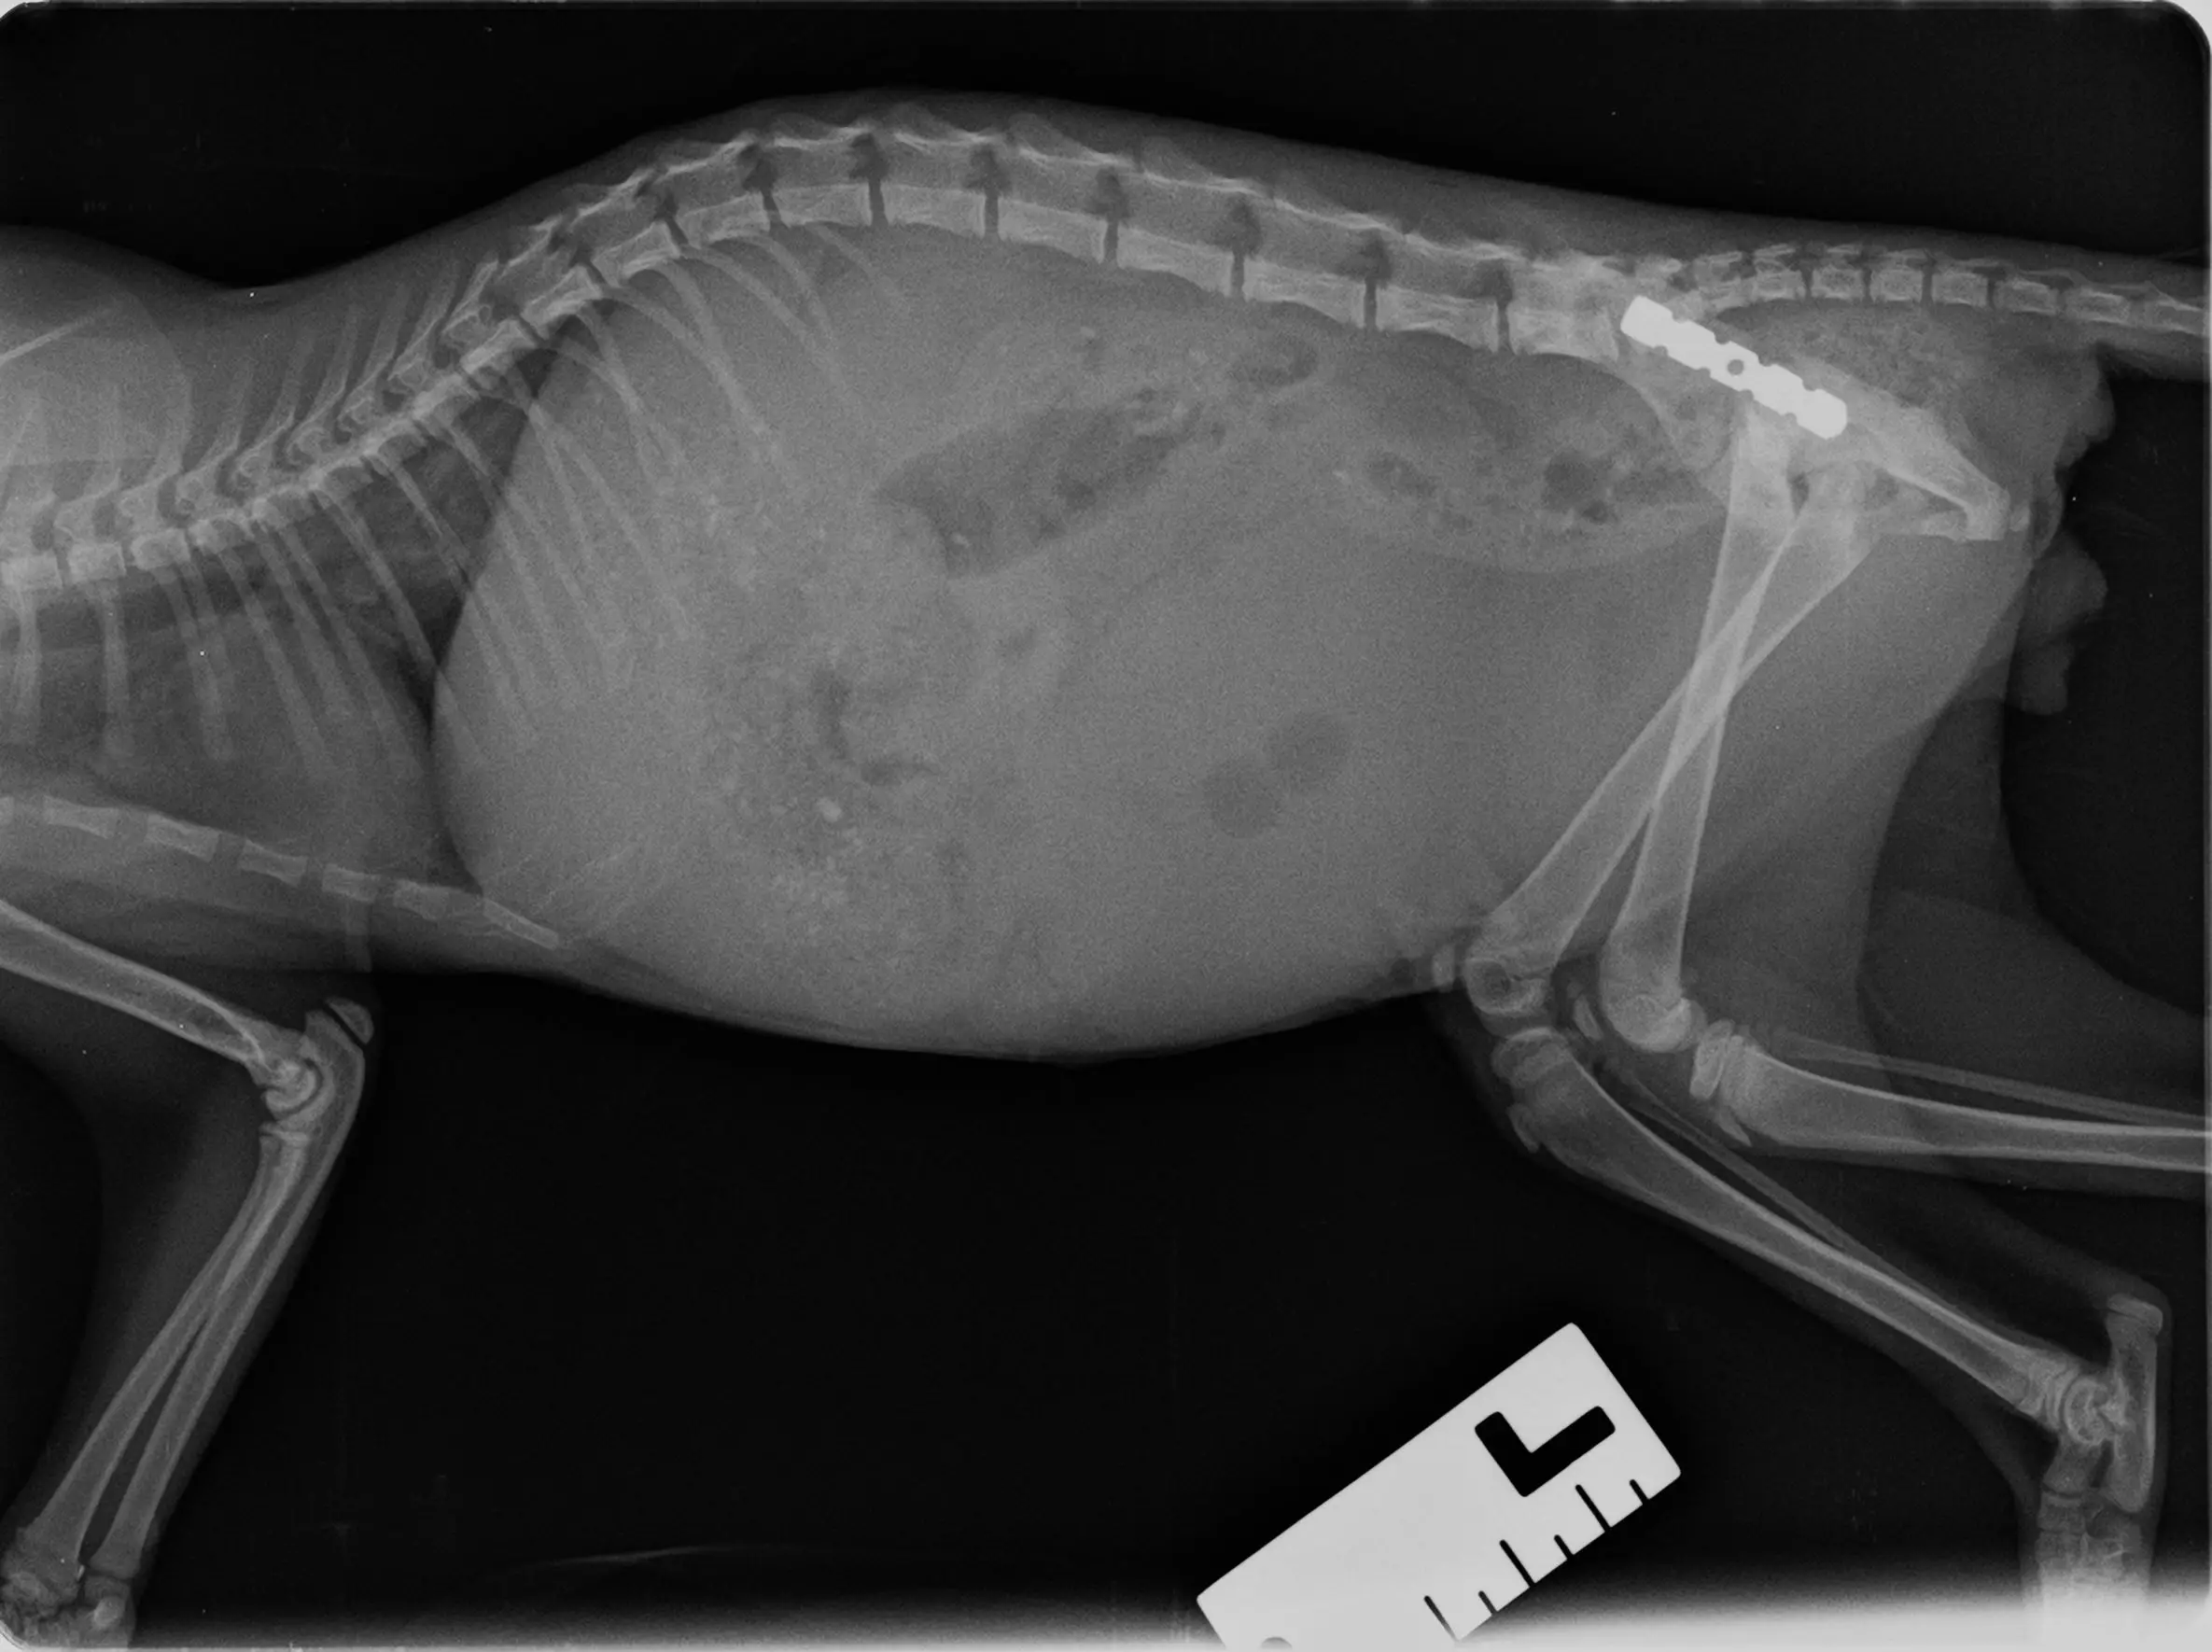

Преди повече от месец, точно пред дома ми съдбата ме срещна с едно безпомощно бебе коте. Беше изхвърлено на улицата – толкова малко, а вече преминало през нечувана болка. Беше ударено жестоко, със счупен таз, видим проблем със задните крачета и много подуто коремче. Заведох го веднага във ветеринарната клиника.

Вече повече от месец е в клиниката, където получава грижи, за да може да се възстанови. За операцията (събиране на таза и поставяне на ортопедични планки), лечението и манипулациите сумата е **2883лв.** като от тях успяхме да съберем и погасим 1233лв. Остават 1650лв – за съжаление това е сума, която за мен е непосилна, а продължава да расте.